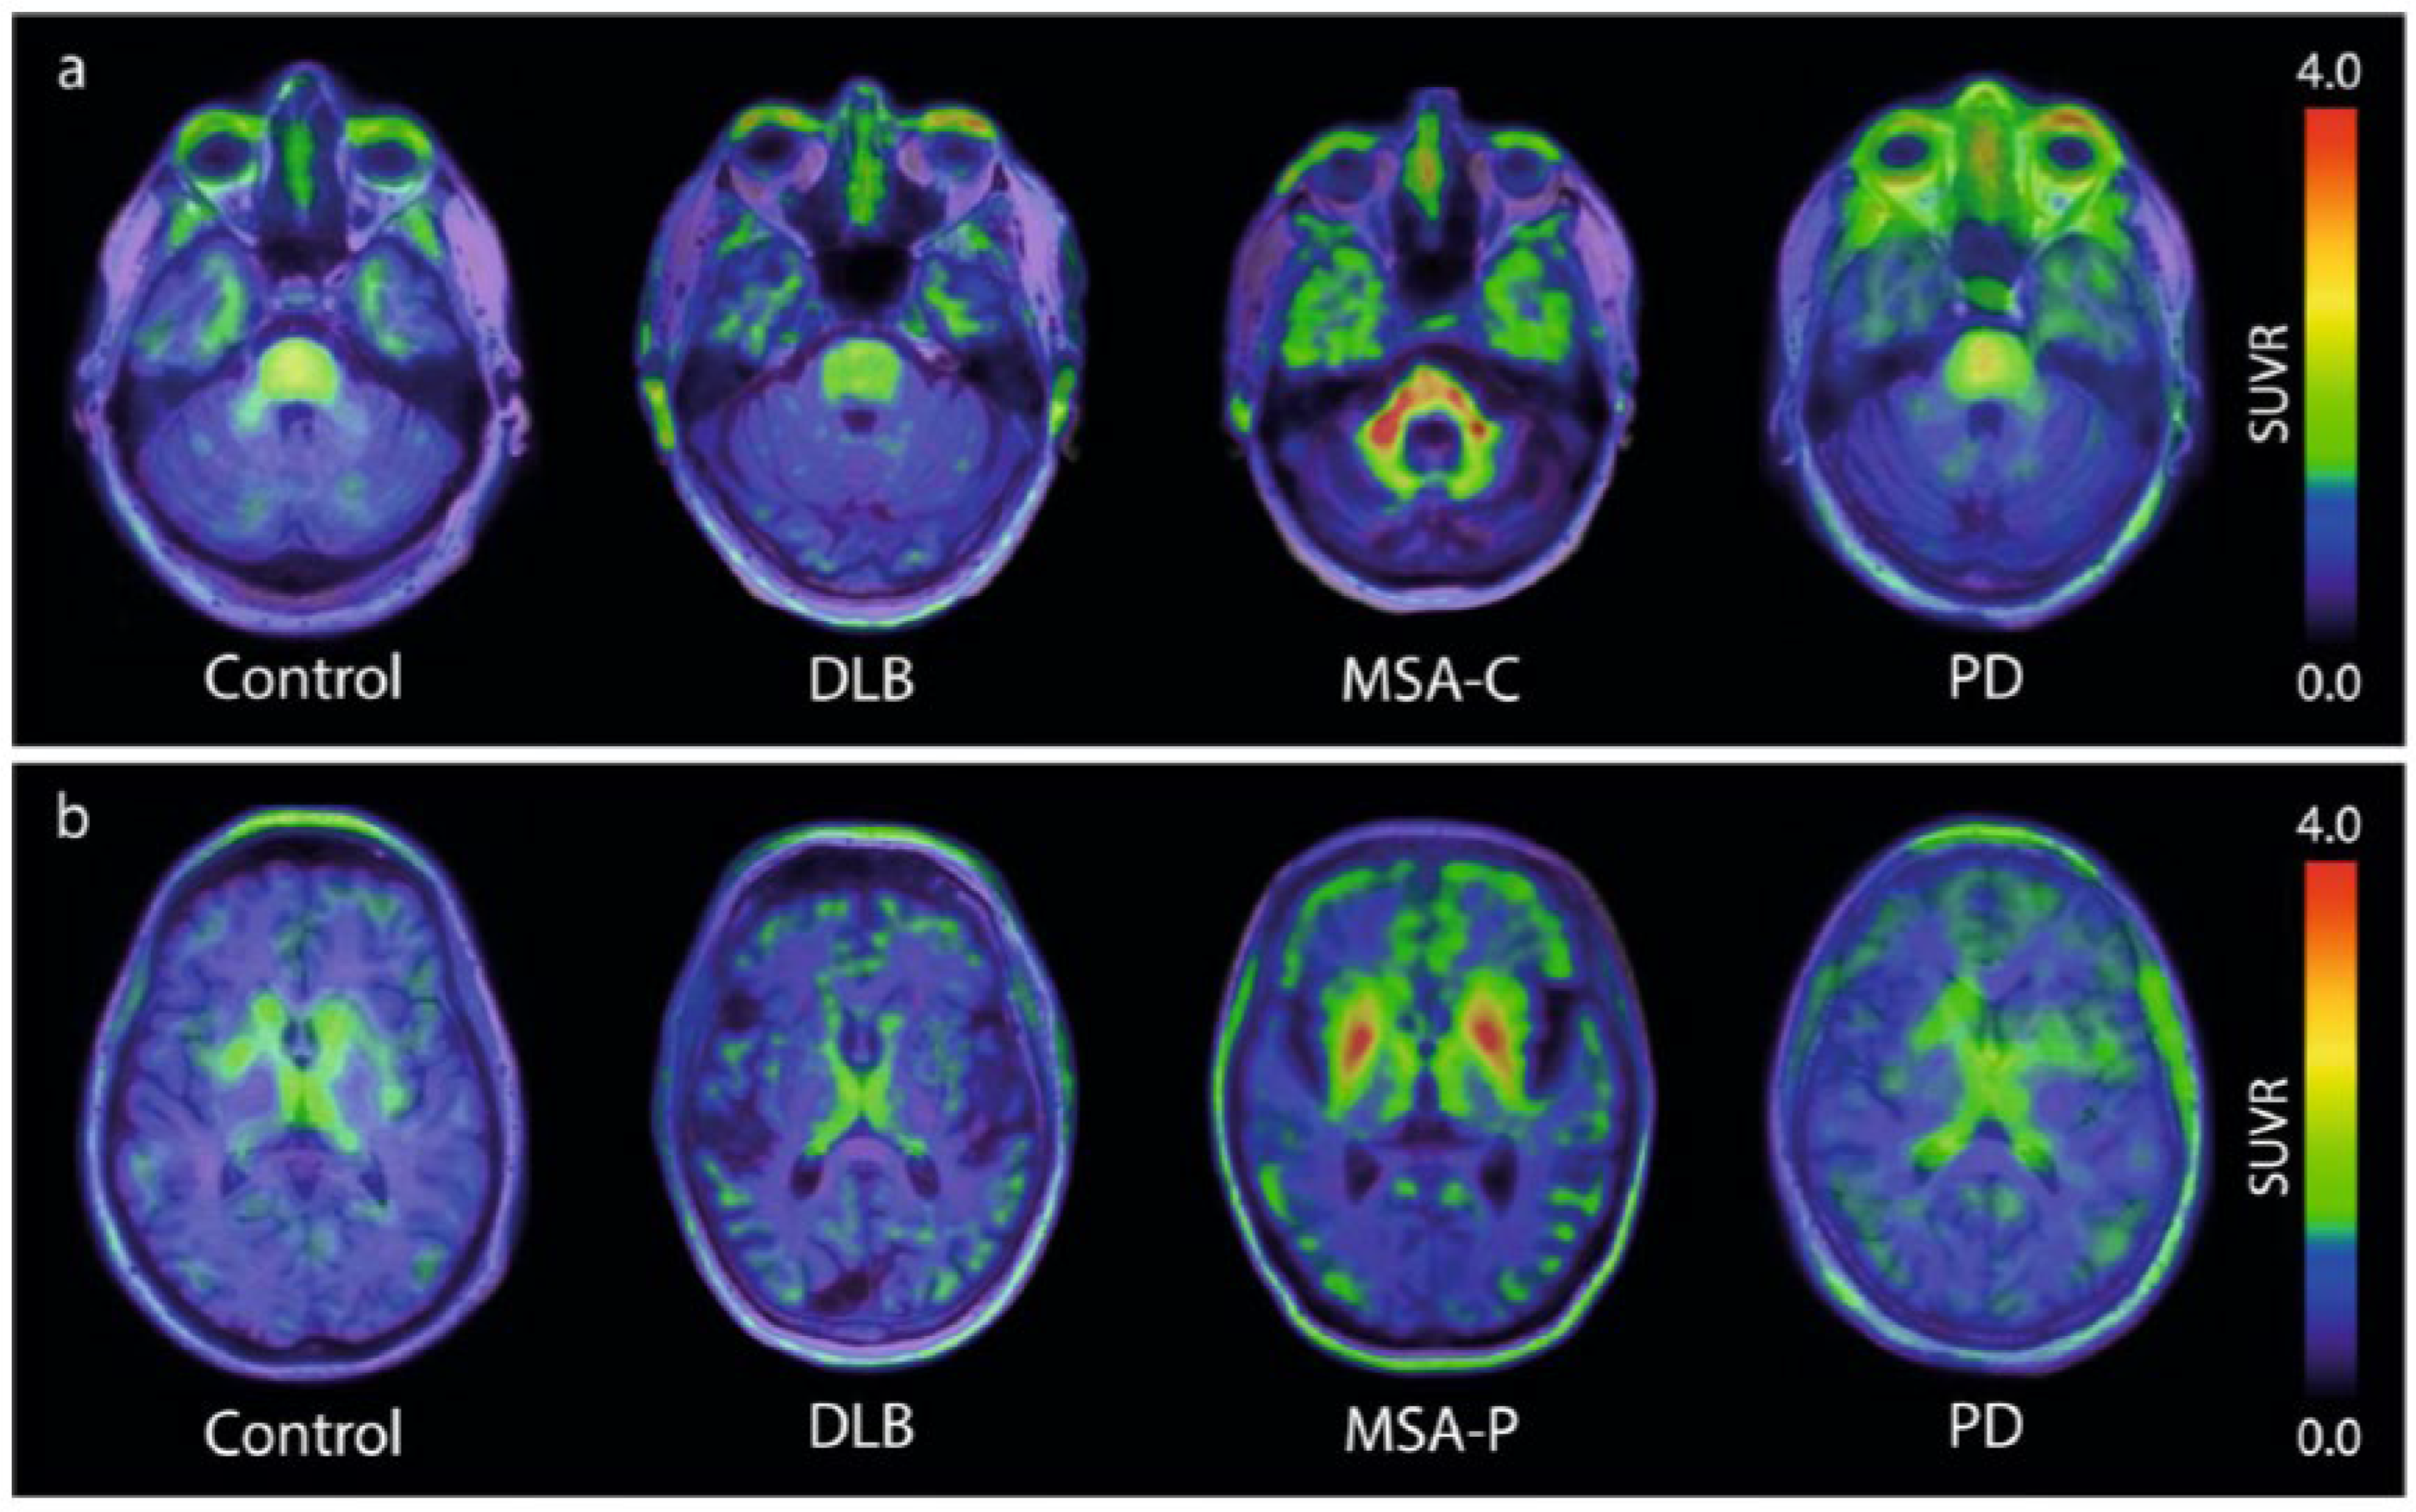

3. State-of-the-Art of the Development of a-synuclein PET Tracers

For many years, different laboratories focused on the identification of new hits, with only a few compounds reaching clinical testing stages. A major breakthrough came in 2023, when, for the first time, the tracer [18F]ACI-12589 finally demonstrated that (i) a-synuclein pathology can be visualized by PET and that (ii) the PET signal can differentiate MSA cases from controls and other neurodegenerative cases [9]. As summarized in Figure 1, this brain-penetrating, low molecular weight compound demonstrated high retention in the cerebellar white matter and middle cerebellar peduncles in cases of MSA dominated by cerebellar ataxia (MSA-C). The same result occurred in cases dominated by Parkinsonism (MSA-P), where tracer uptake was also observed in the lentiform nuclei. These observations correlated well with the expected distribution of the a-synuclein pathology in both MSA subtypes, a conclusion based on post-mortem data and clinical presentations [19,20]. With the publication of these first PET images of the a-synuclein pathology in patients diagnosed with MSA, the field finally had a benchmark proving the feasibility of detecting a-synuclein pathology via PET.

Figure 1. [18F]ACI-12589 PET in participants with synucleinopathies. (a) Presentative transversal images from [9] at the level of the middle cerebellar peduncles in a control participant, and patients with DLB, MSA-C and PD. (b) Representative transversal images from [9] at the level of the basal ganglia in a control participant, and patients with DLB, MSA-P and PD. SUVR images for (a,b) are averaged for the 60–90 min time frame and have been created using occipital cortex as a reference region.